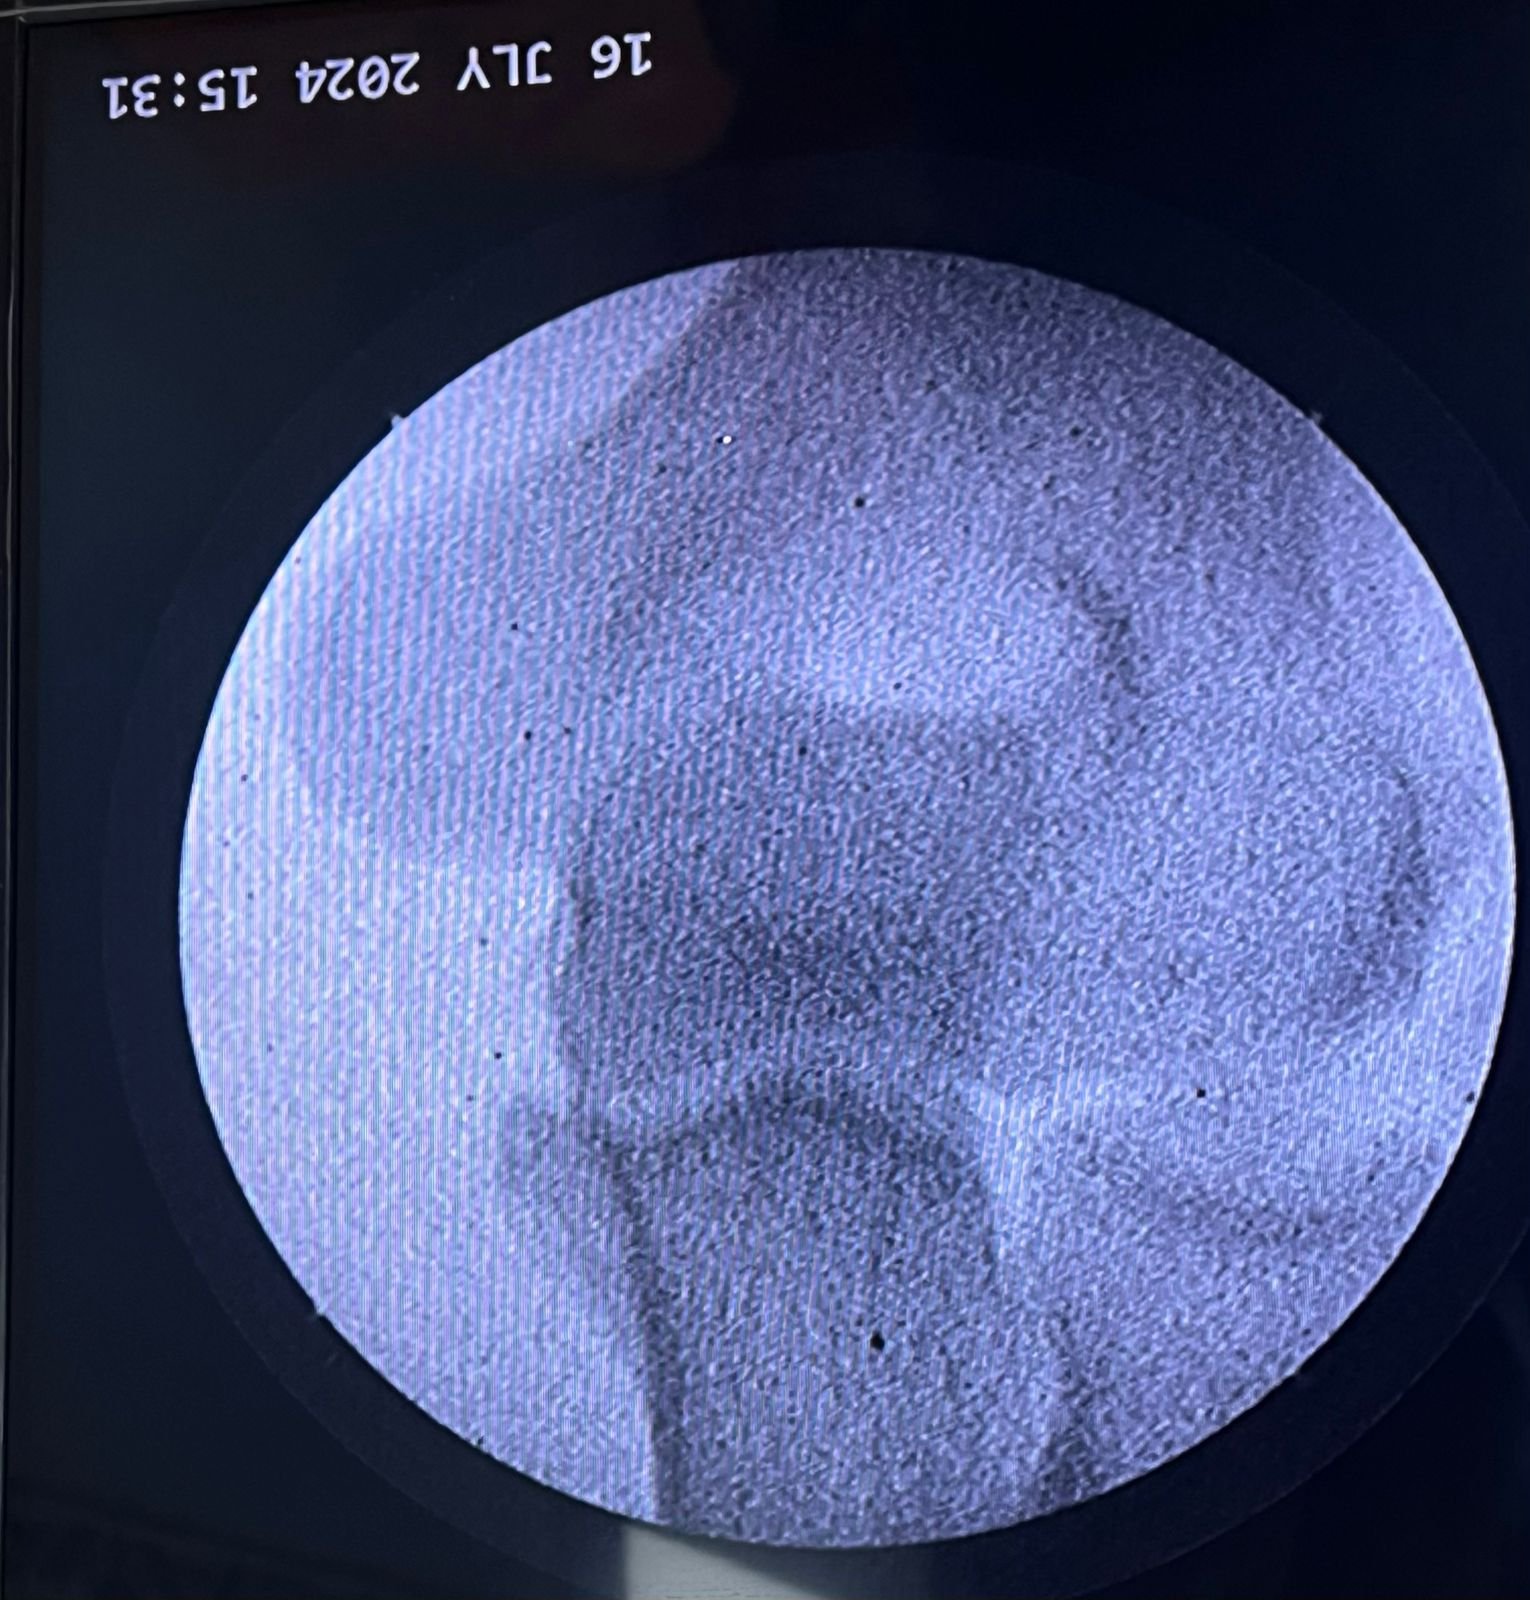

Clinic Exterior & Reception | Elbow dislocation &

operative treatment